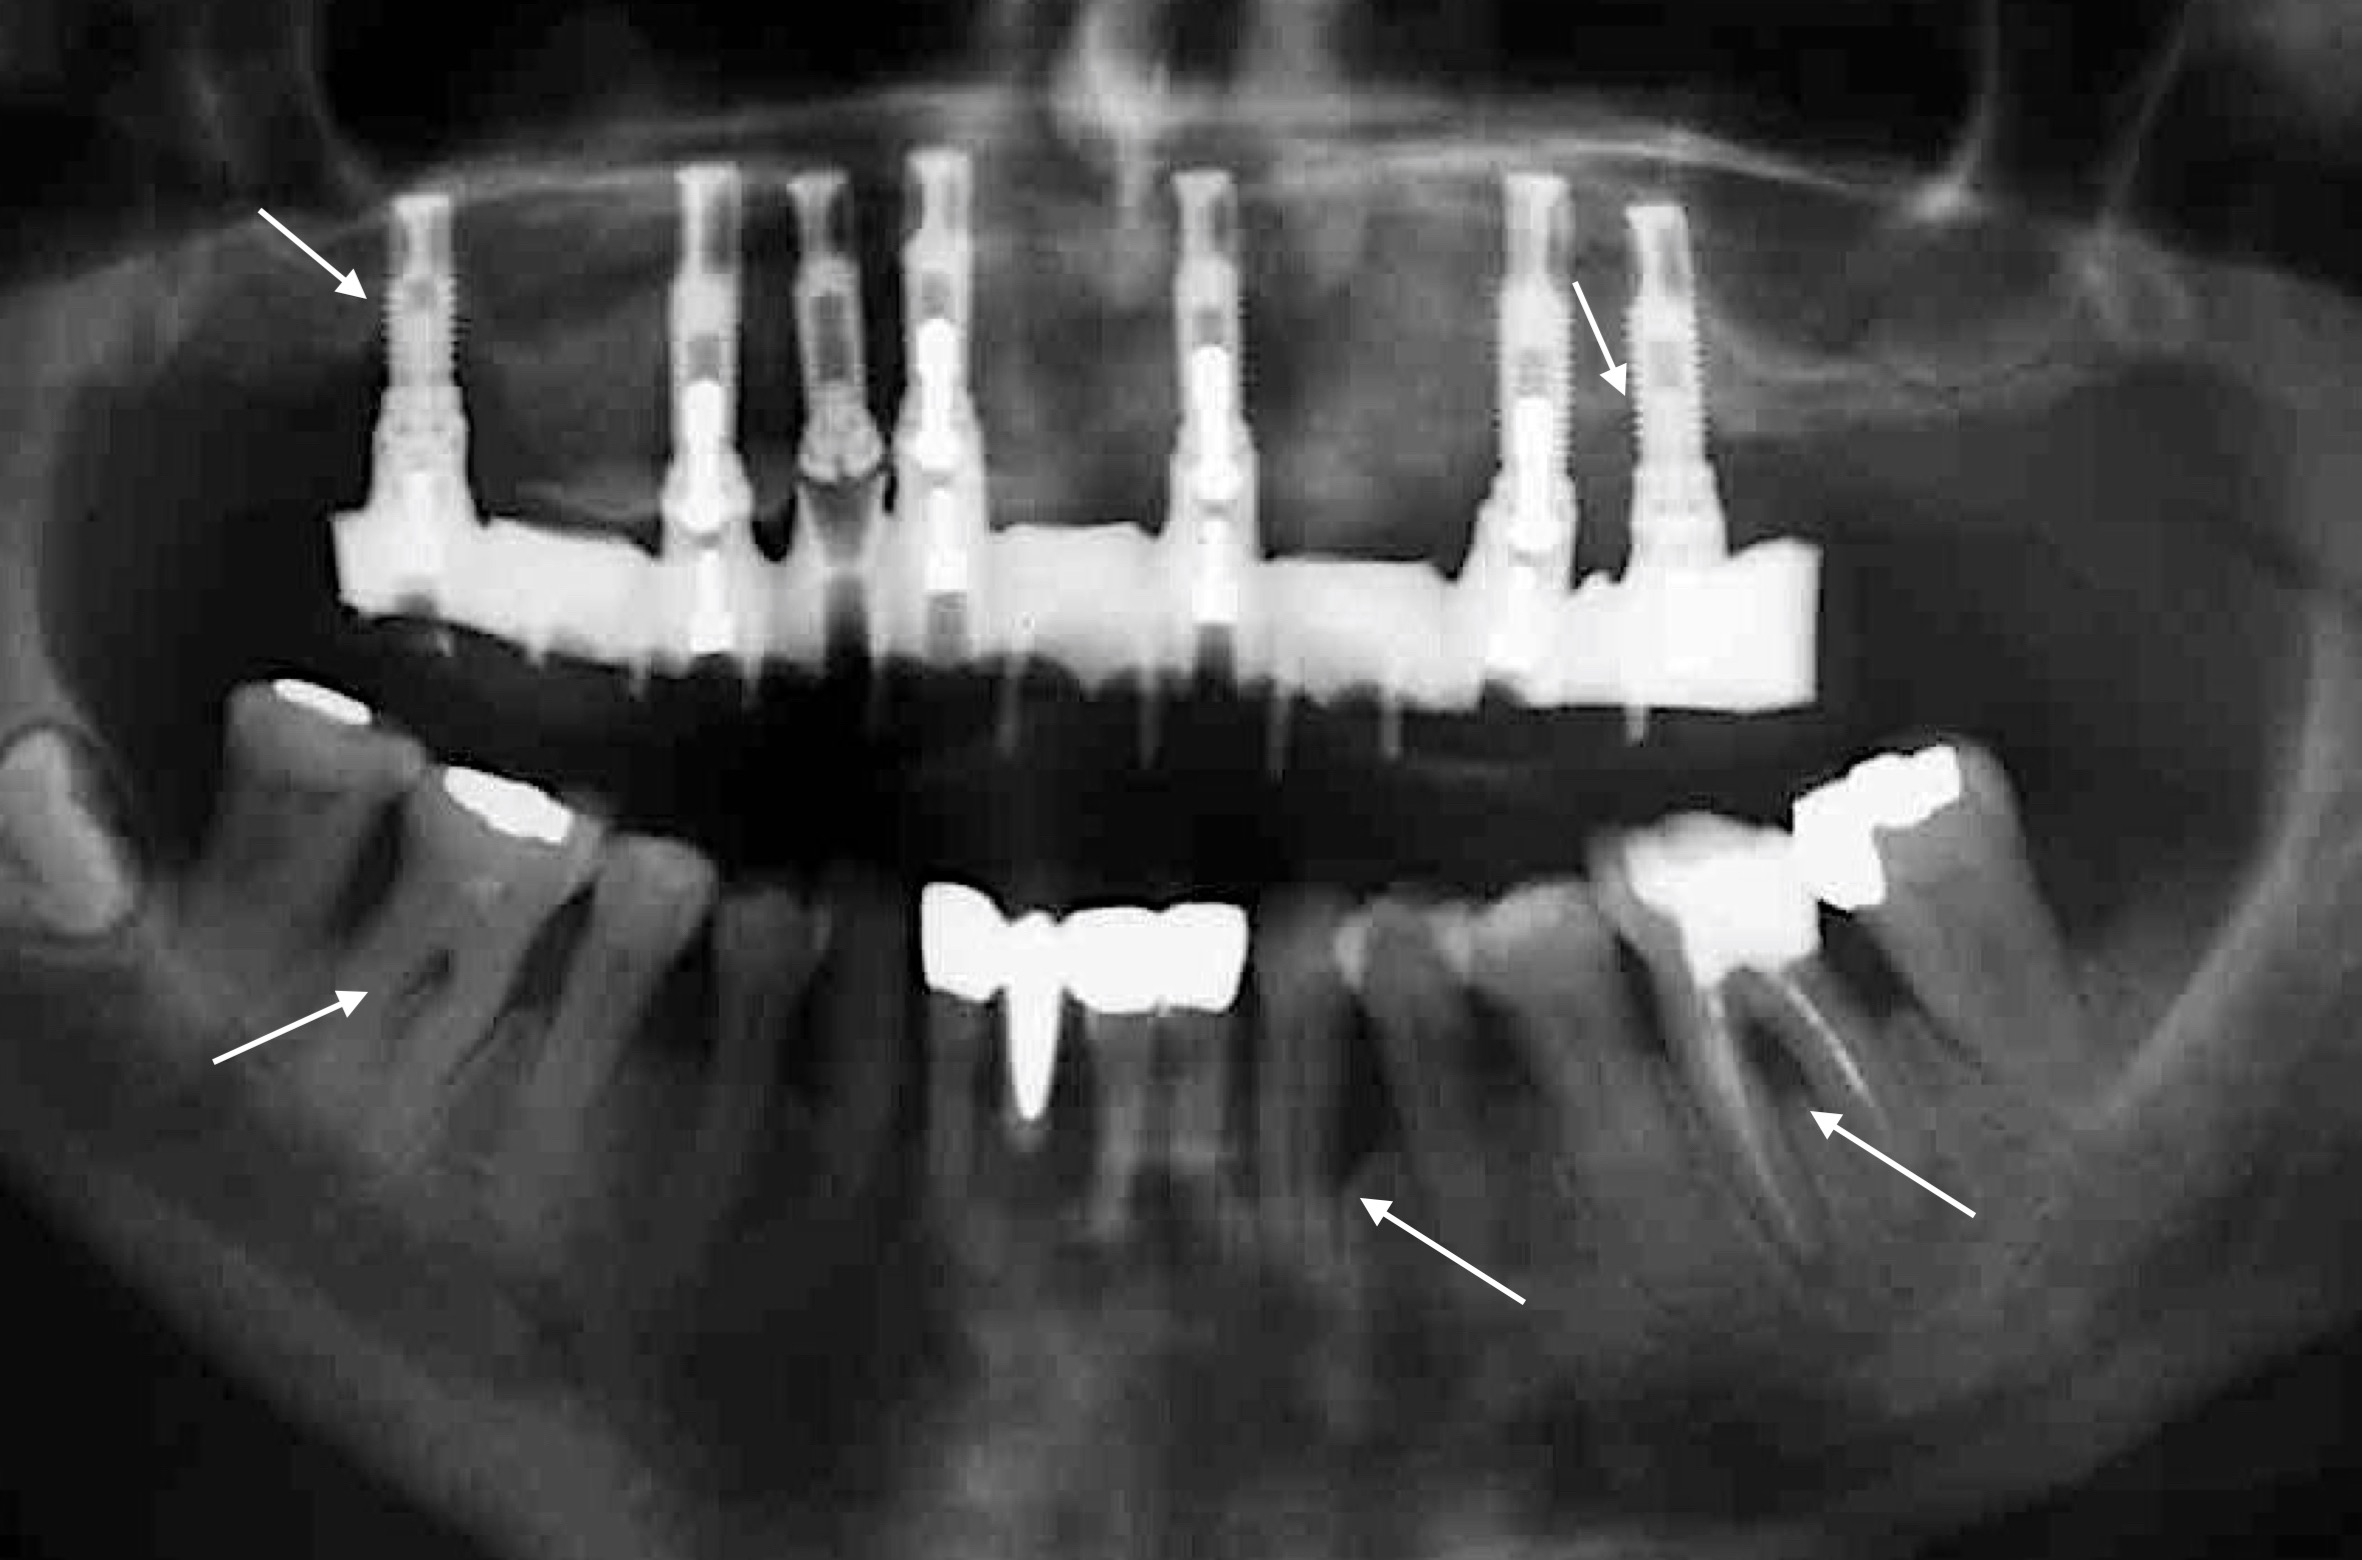

Doch wie hoch ist das Risiko bei Parodontitis-PatientInnen auch eine peri-implantäre Mukositis oder gar Peri-implantitis zu entwickeln und im schlimmsten Fall einen Implantatmisserfolg zu erleiden – kleiner, gleich, oder doch größer …?

Zahlreiche Übersichtsarbeiten der letzten 10 Jahre belegen ein höheres Risiko eines Implantatmisserfolgs bei PatientInnen mit parodontaler Grunderkrankung (z.B.: Renvert & Persson 2009, Sousa et al. 2016, uvm.) und dieses Risiko scheint bei PatientInnen mit der Diagnose „generalisierte aggressive Parodontitis“ noch zusätzlich erhöht zu sein (Monje et al. 2016). Um diese Komplikation möglichst zu vermeiden, gilt es den/die Patienten/Patientin parodontal möglichst gut im Griff zu halten! Das bedeutet: 1) Die parodontale Therapie muss vor der Implantattherapie stattfinden; 2) Strikte Optimierung der Mundhygiene und vor allem gezielte Re-instruktion nach Eingliederung der Implantat-getragenen Versorgung; 3) Planung und Durchführung regelmäßiger Recallsitzungen um einerseits kein Rezidiv in Bezug auf die Parodontitis zu erleiden und andererseits peri-implantäre Erkrankungen frühzeitig zu erkennen; und 4) Rest-Sondierungstiefen nach der parodontalen Therapie möglichst vermeiden! Warum ist letzteres so wichtig? Eine Studie aus Australien (Cho-Yan Lee et al. 2012) hat sehr schön gezeigt, dass das Risiko eine Peri-implantitis zu entwickeln bei Parodontitis-PatientInnen mit Restsondierungstiefen (≥ 6mm Sondierungstiefe) im Vergleich zu Parodontitis-PatientInnen ohne Restsondierungstiefen und parodontal gesunden PatientInnen 4- bis 5-fach erhöht ist!

Nichtsdestotrotz sollte man nicht nur die negativen Aspekte sehen, denn man kann natürlich auch bei Parodontitis-PatientInnen eine hohe Implantatüberlebensrate von rund 92 % nach 10 Jahren erzielen (Zangrando et al. 2015)!